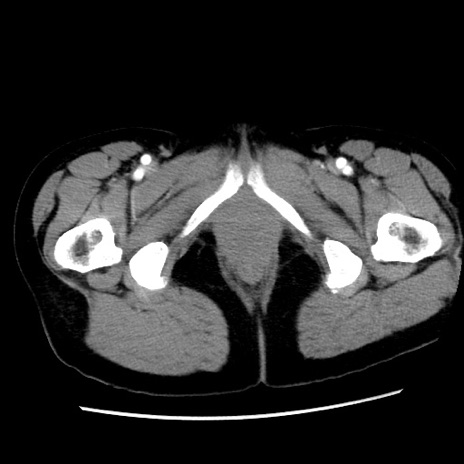

症例10(横断像)

【症例】 50歳代女性

【主訴】 腹痛

【現病歴】前日生レバーを食べた。今朝に排便あり。 昼前に突然発症の腹痛を生じ、当院救急外来を受診した。

【既往歴】 子宮筋腫にてで子宮全摘後

【身体所見】 意識清明、腹部:平坦、軟、下腹部やや左を中心に圧痛・反跳痛あり、筋性防御あり

【データ】WBC 7800、CRP 0.07